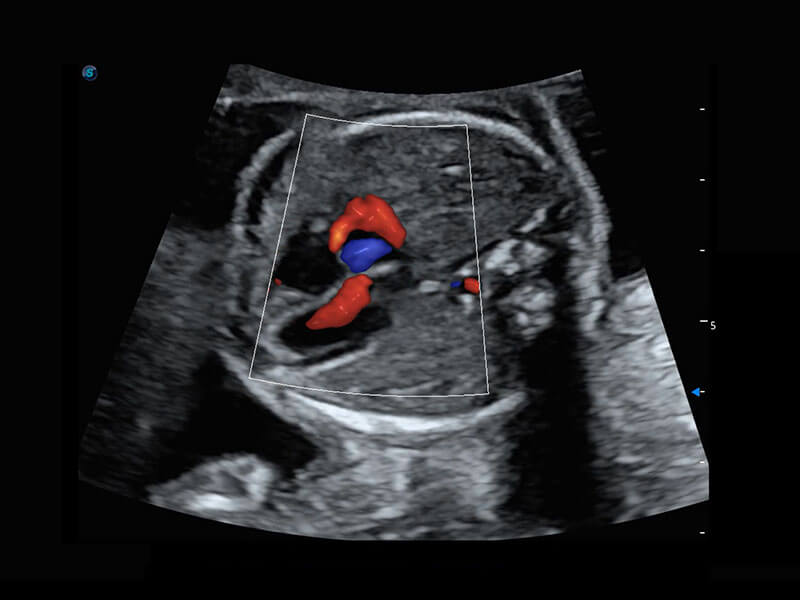

P60搭載一系列胎兒心臟成像技術(shù),實現(xiàn)精細的胎兒心臟評估。

四腔切面

四腔心血流

右室雙出口

胎心容積成像